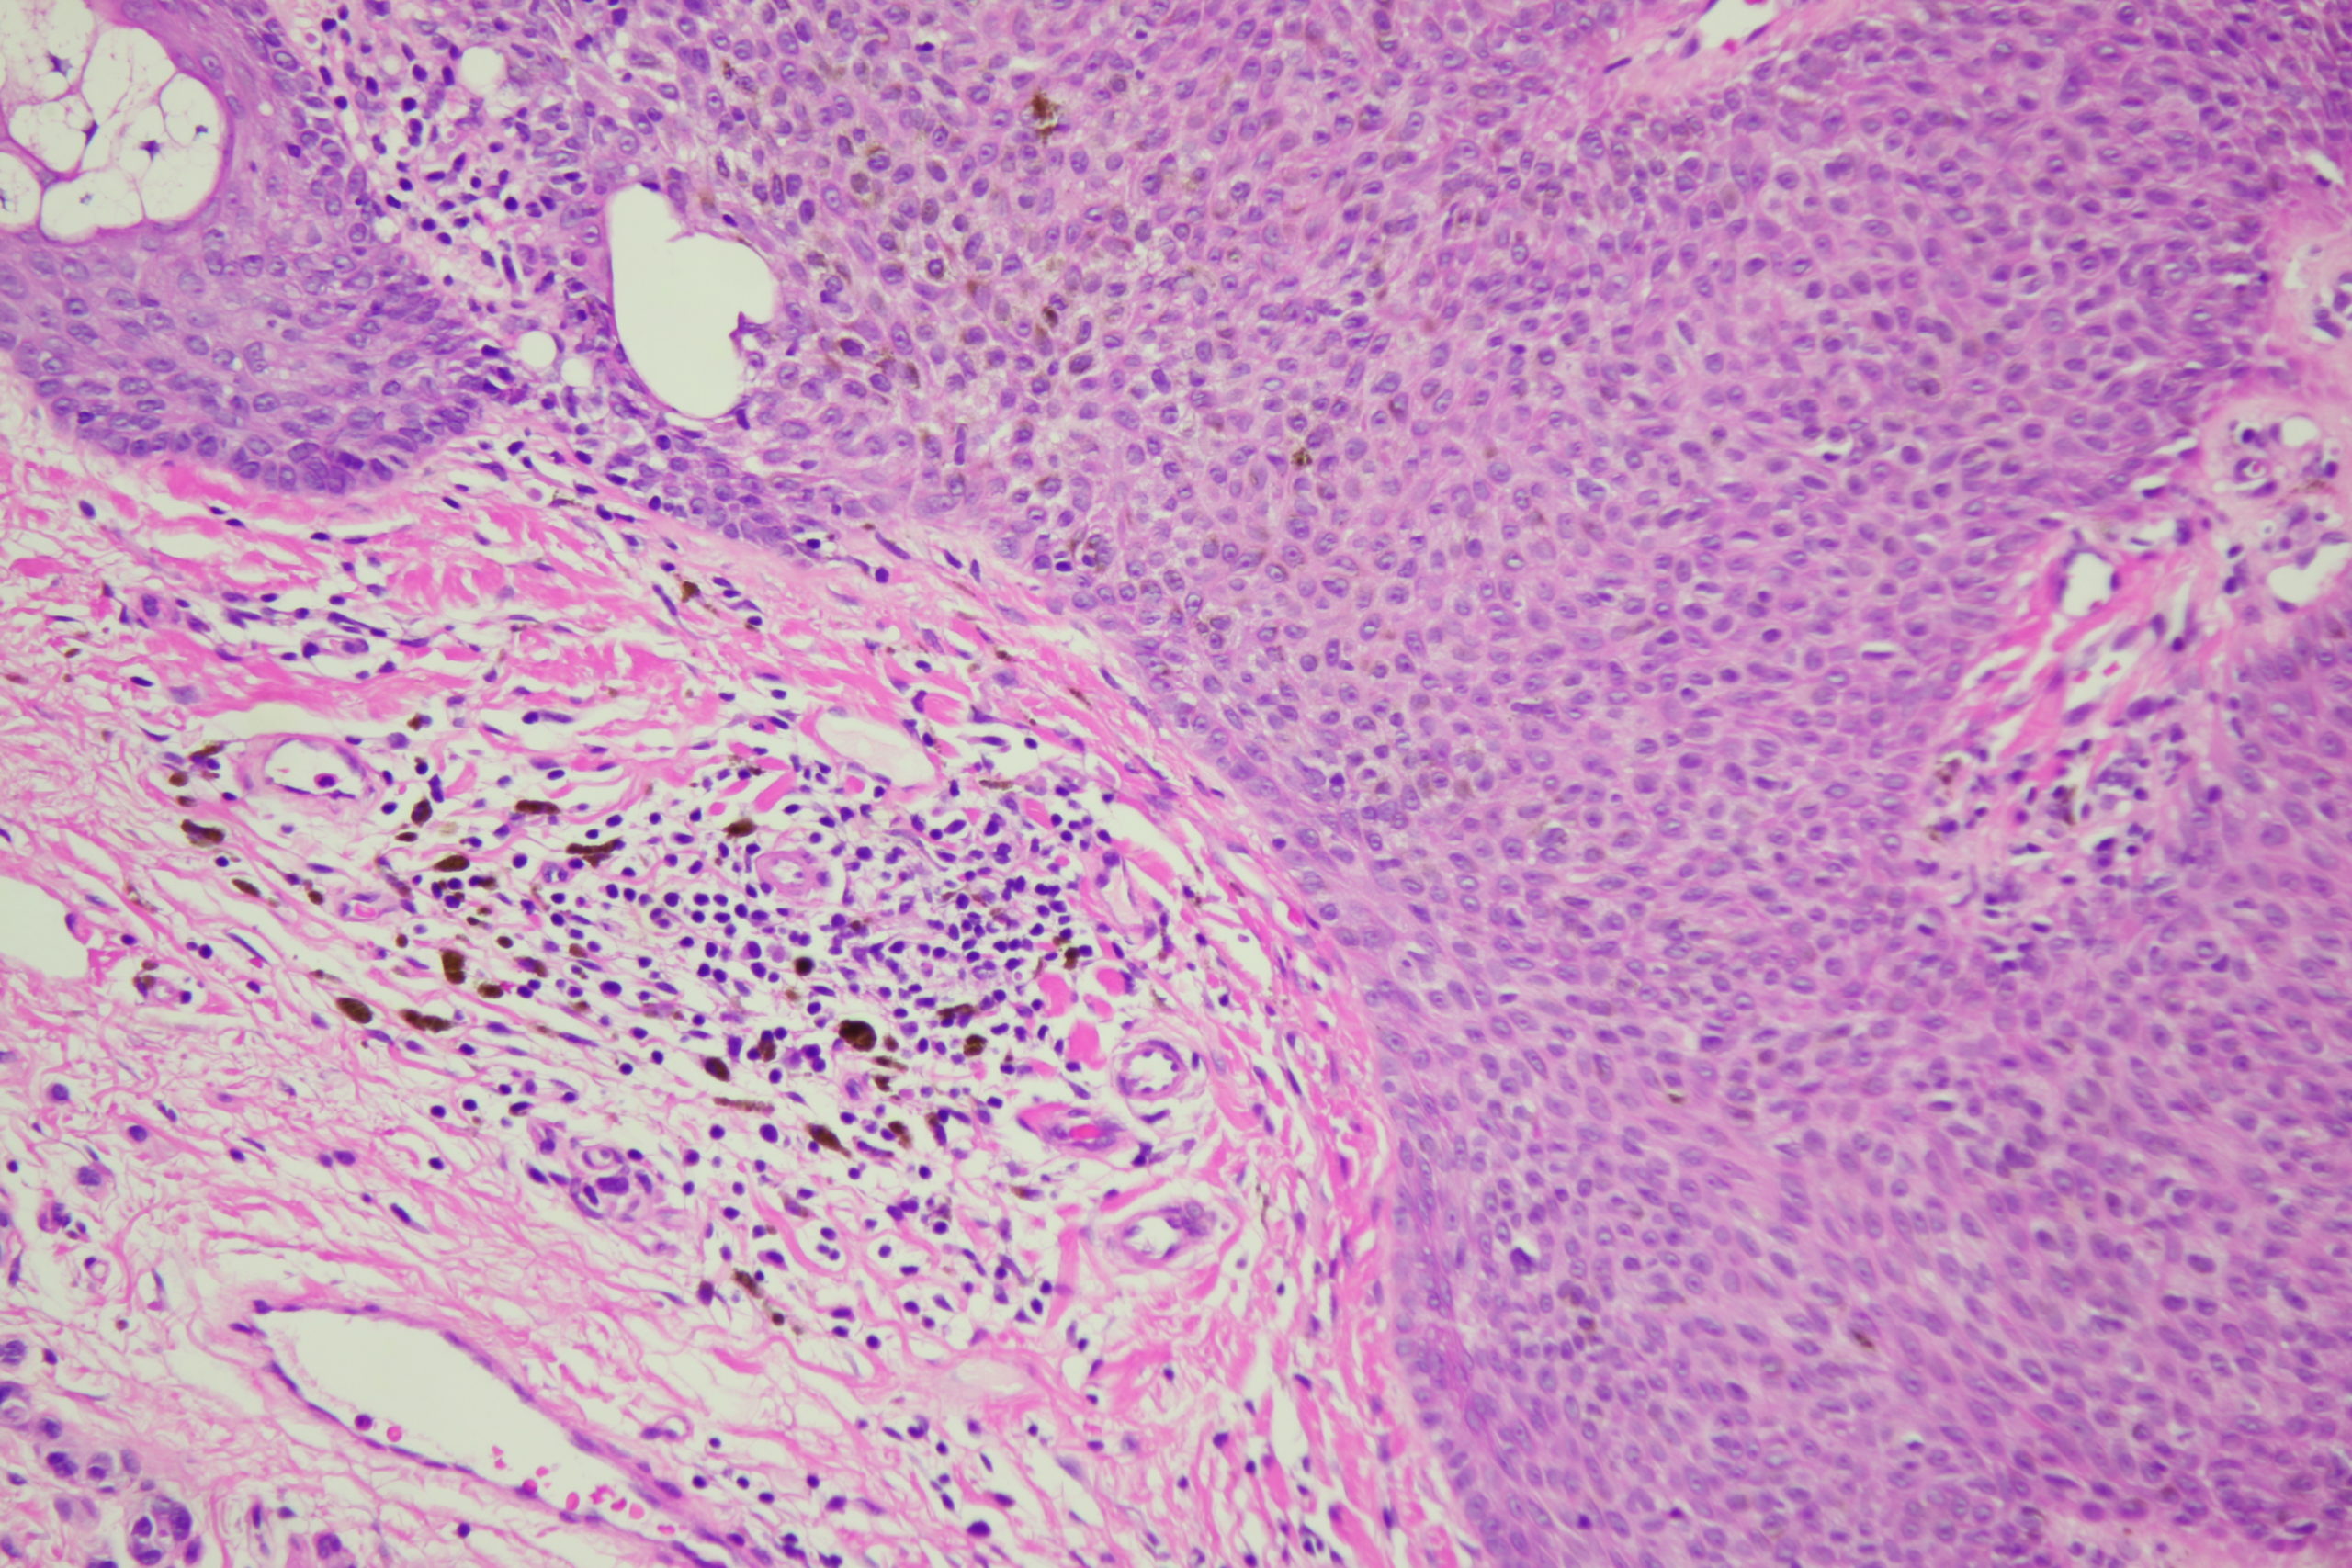

Site: Back

Diagnosis: Seborrhoeic keratosis irritated

Age: 72

Description: Dark blue blackish structureless areas surrounding paler center and white surface scales Broad coarse fatty brownish radial circumferential structures and black dots

A man in his 70s with this pigmented lesion on his upper back noted during a skin check.I look carefully at all dark seb k like lesions because lentigo maligna can easily involve a seb k. However I am always concerned about missing a seb k like melanoma. What do you think of this one? Note the pink colour surrounding it.